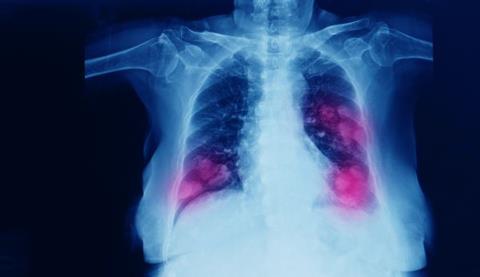

French pharmaceutical giant Sanofi announced that it is ending the development programme evaluating tusamitamab ravtansine as a monotherapy for certain patients with metastatic non-squamous, non-small cell lung cancer (NSCLC).

CARMEN-LC03, a randomised, open-label study was evaluating tusamitamab ravtansine as monotherapy compared to docetaxel in patients with metastatic non-squamous NSCLC whose tumours express high levels of carcinoembryonic antigen-related cell adhesion molecule 5 (CEACAM5).